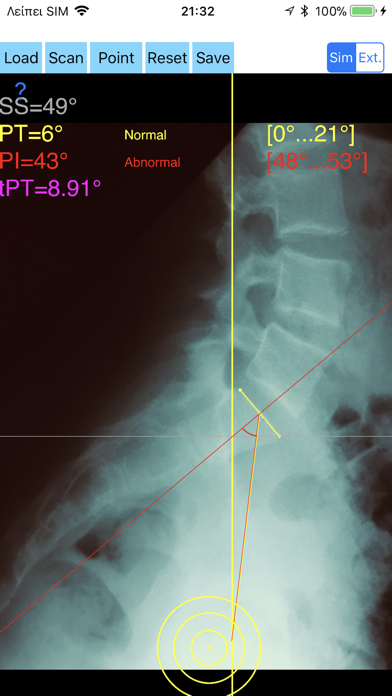

1. -By marking few points at the image of X-ray, the App calculates and offers a very convenient way to determine the most accurate possibly way at once, Pelvic incidence (PI), Sacral slope (SS), Pelvic Tilt (PT), Lumbar lordosis (LL), thoracic kyphosis, PI–LL Pelvic incidence Angle (PI) minus Lumbar lordosis Angle (LL) PI–LL, theoretical normal pelvic tilt (tPT),theoretical normal L1-S1 lumbar lordosis (tL1S1), Pelvic Radius Angle (PRA).

2. Radiographic parameters to evaluate objectively the spinopelvic sagittal balance are Pelvic incidence (PI), Sacral slope (SS), Pelvic Tilt (PT), Lumbar lordosis (LL).

3. -The app offers theoretical value estimation this is particularly useful because a sensible difference between theoretical value and measured value reveals a compensation phenomenon if the pelvis tilt (PT) is higher than its theoretical value, then it is due to pelvis retroversion, which is a compensation phenomenon.

4. Knowing the theoretical value of Pelvis Tilt (PT) provided it is easy to understand that a sensible difference between theoretical value and measured value is a compensation phenomenon.

8. The app offers a very convenient and accurate way to perform most common radiographic measurements for spine, at the spinopelvic juncture in a blink of an eye in front of your screen.

10. -The app allows choosing between simple and extended method according to everyday preference and also by choosing points in vertebra body in a independent manner from order.

11. According to measured parameters the app categorises the severity of the imbalance of spine, in different stages: optimal or non optimal.